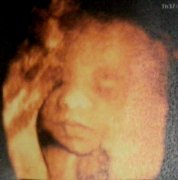

子宫内膜道图

子宫内膜炎

上一篇:四维彩超胎儿图片     下一篇:我想看一下腰椎间盘突出图片